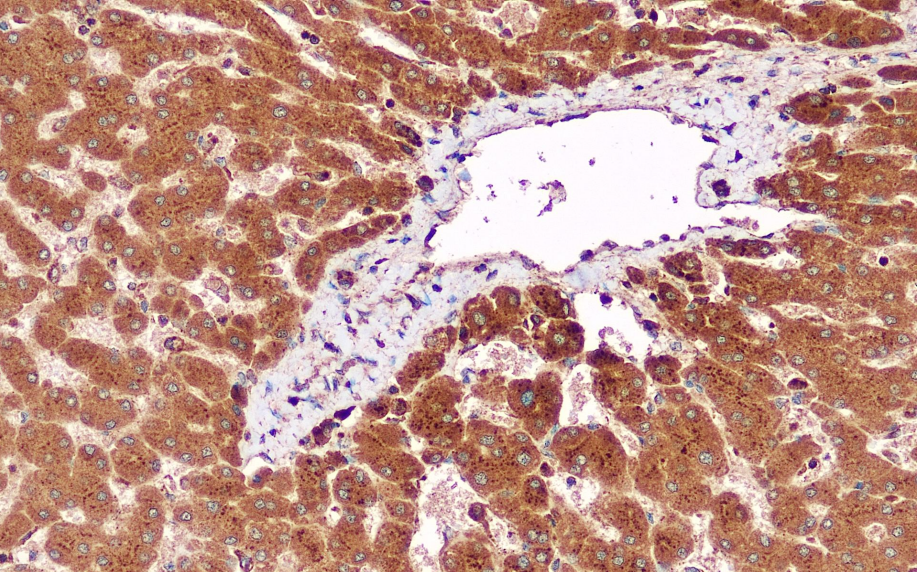

Positive Control: Liver

VEGF is a protein with a molecular weight of 34–50 kDa, synthesized by tumor cells, vascular endothelial cells, and macrophages. It acts specifically on receptors on vascular endothelial cells through autocrine/paracrine mechanisms, promoting endothelial cell growth, proliferation, migration, extracellular matrix degradation, and the formation of vascular tubular structures. Among numerous vascular regenerative factors, VEGF and its receptors are recognized as key mediators of angiogenesis, strongly promoting endothelial mitosis and the formation of new blood vessels. It is a potent cytokine stimulating tumor angiogenesis. This antibody recognizes VEGF and is primarily used for studying the relationship between angiogenesis and tumor metastasis in various tumor tissues.

VEGF antibody reagents can specifically bind to VEGF molecular antigens. Immunohistochemistry kits containing VEGF antibody reagents are suitable for assessing tumor angiogenesis (such as colorectal cancer and renal cancer) and predicting the efficacy of anti-VEGF targeted therapy (such as bevacizumab).